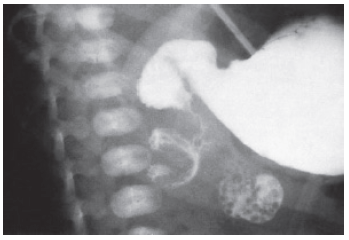

Durante o plantão numa maternidade de baixo risco um médico avalia um recém nascido a termo, de 24 horas de vida, sem intercorrências na gestação. Nascido de parto vaginal, peso 3,4 kg, Apgar 9/10, está no alojamento conjunto, em aleitamento materno exclusivo. A mãe refere que seu filho apresentou dois episódios de vômitos biliosos durante o dia e que está recusando o seio. Ao exame clínico, tem o abdomen distendido e doloroso e o cateter nasogástrico dá saída à secreção biliar e sanguinolenta. Após o toque retal há saída de sangue enegrecido. Uma radiografia simples de abdômen revela distribuição gasosa irregular, presente no estômago e na primeira porção do duodeno, sem gás no restante do abdômen. Em sua maternidade, não há cirurgiões, mas o radiologista de plantão realiza uma serigrafia, visualizada na figura a seguir. enunciado 391377-1

Ao solicitar a transferência do recém nascido para um hospital de maior complexidade, baseado nos dados de história, exames clínico e radiológico, o médico deve indicar como diagnóstico provável: